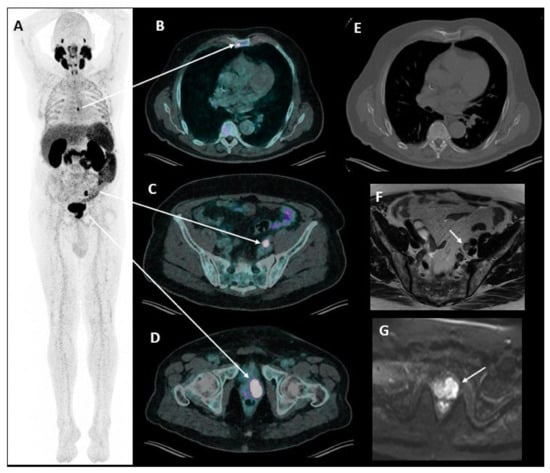

4.4. Prostate Cancer

2.5.3. Metabolic and Receptor-Specific Imaging

2.5.4. Combined Modalities